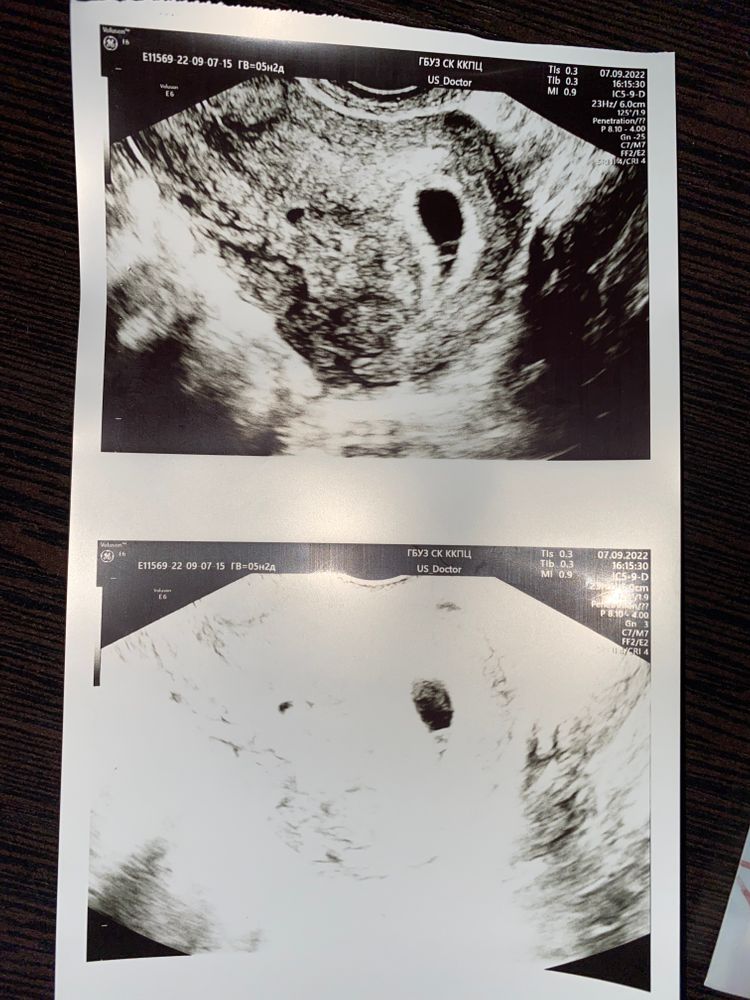

Была во вторник на узи нашли отслойку или гематому так и не поняла небольшую. 4 дня лежу почти не вставая. Вставляю утро-вечер утрожестан. Когда лежу ничего можно сказать не тянет, не болит, как только встаю начинает тянуть то правый, то левый яичник и прям нормально так. У кого было так, все нормально закончилось? Когда сильно тянет вставляю папаверин.